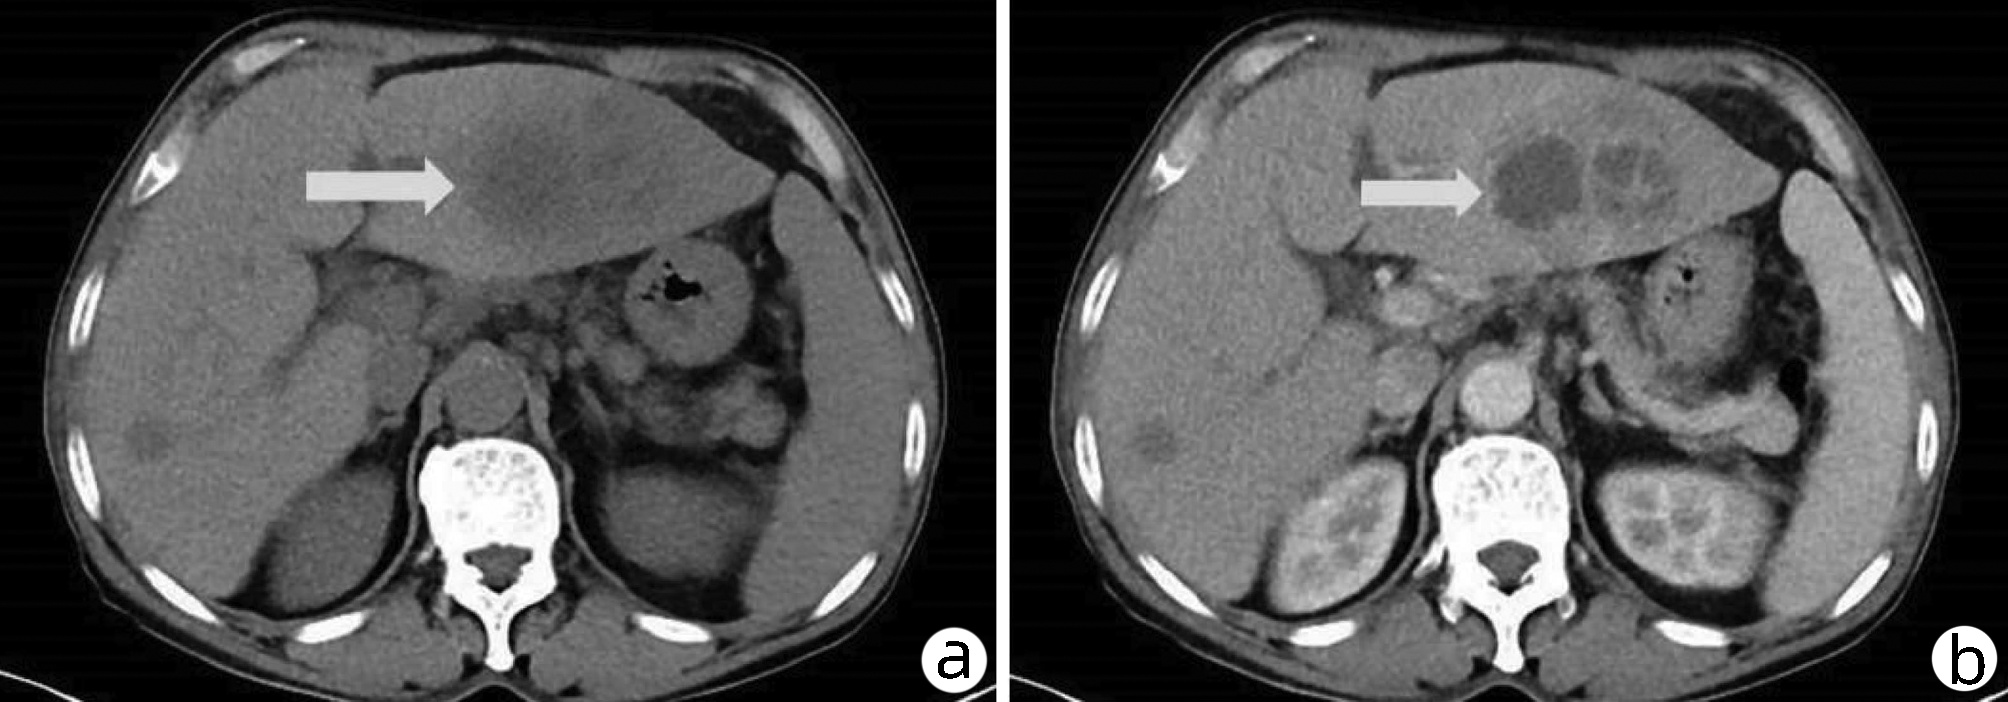

Ultrasound findings and contrast-enhanced ultrasound findings of mass-type autoimmune pancreatitis versus pancreatic ductal adenocarcinoma

Xiangliu OUYANG, Yunxia HAN, Lichun ZHENG, Yingchun ZHAO, Xinyu SHEN, Wenjun ZHANG, Yanbin WANG

2022, 38(6): 1351-1355. DOI: 10.3969/j.issn.1001-5256.2022.06.025

Abstract(1427) HTML (553) PDF (3738KB)(50)

Abstract:

Objective  To investigate the value of ultrasound and contrast-enhanced ultrasound (CEUS) in the differential diagnosis of mass-type autoimmune pancreatitis (AIP) and pancreatic ductal adenocarcinoma (PDAC).  Methods  A retrospective analysis was performed for the clinical data, ultrasound findings, and CEUS findings of 11 patients with mass-type AIP who were diagnosed in Tangshan Workers' Hospital from January 2015 to December 2020, and their characteristic manifestations were analyzed and compared with the data of 23 patients with PDCA. The chi-square test was used for comparison of categorical data between two groups.  Results  For the 11 patients with mass-type AIP, CEUS had a diagnostic accuracy of 63.64%, and all of these patients had hypoechoic single lesions; the patients with clear boundaries, regular morphology, pancreatic duct dilatation or cutoff, and blood flow signal accounted for 54.55%, 63.64%, 18.18%, and 36.36%, respectively, while in the PDCA group, such patients accounted for 30.43%, 34.78%, 78.26%, and 21.74%, respectively, and there was a significant difference in the presence or absence of pancreatic duct dilatation or cutoff between the two groups(χ2=11.089, P < 0.05), with no significant differences in the other indices (all P > 0.05). For the 11 patients with mass-type AIP, CEUS showed that 7 patients (63.64%) had hyperenhancement and 4 (36.36%) had iso-enhancement in the arterial phase, and 5 patients (45.45%) had hyperenhancement in the arterial phase and 6 (54.55%) had iso-enhancement in the venous phase; for the 23 patients with PDCA, 22 (95.65%) had hypoenhancement of lesions in both arterial and venous phases, and there were significant differences in the enhancement pattern in arterial and venous phases between the two groups (χ2=30.345 and 30.084, both P < 0.05).  Conclusion  The enhancement pattern of CEUS and the presence or absence of pancreatic duct dilatation or cutoff have a relatively high value in the differential diagnosis of mass-type AIP and PDCA.